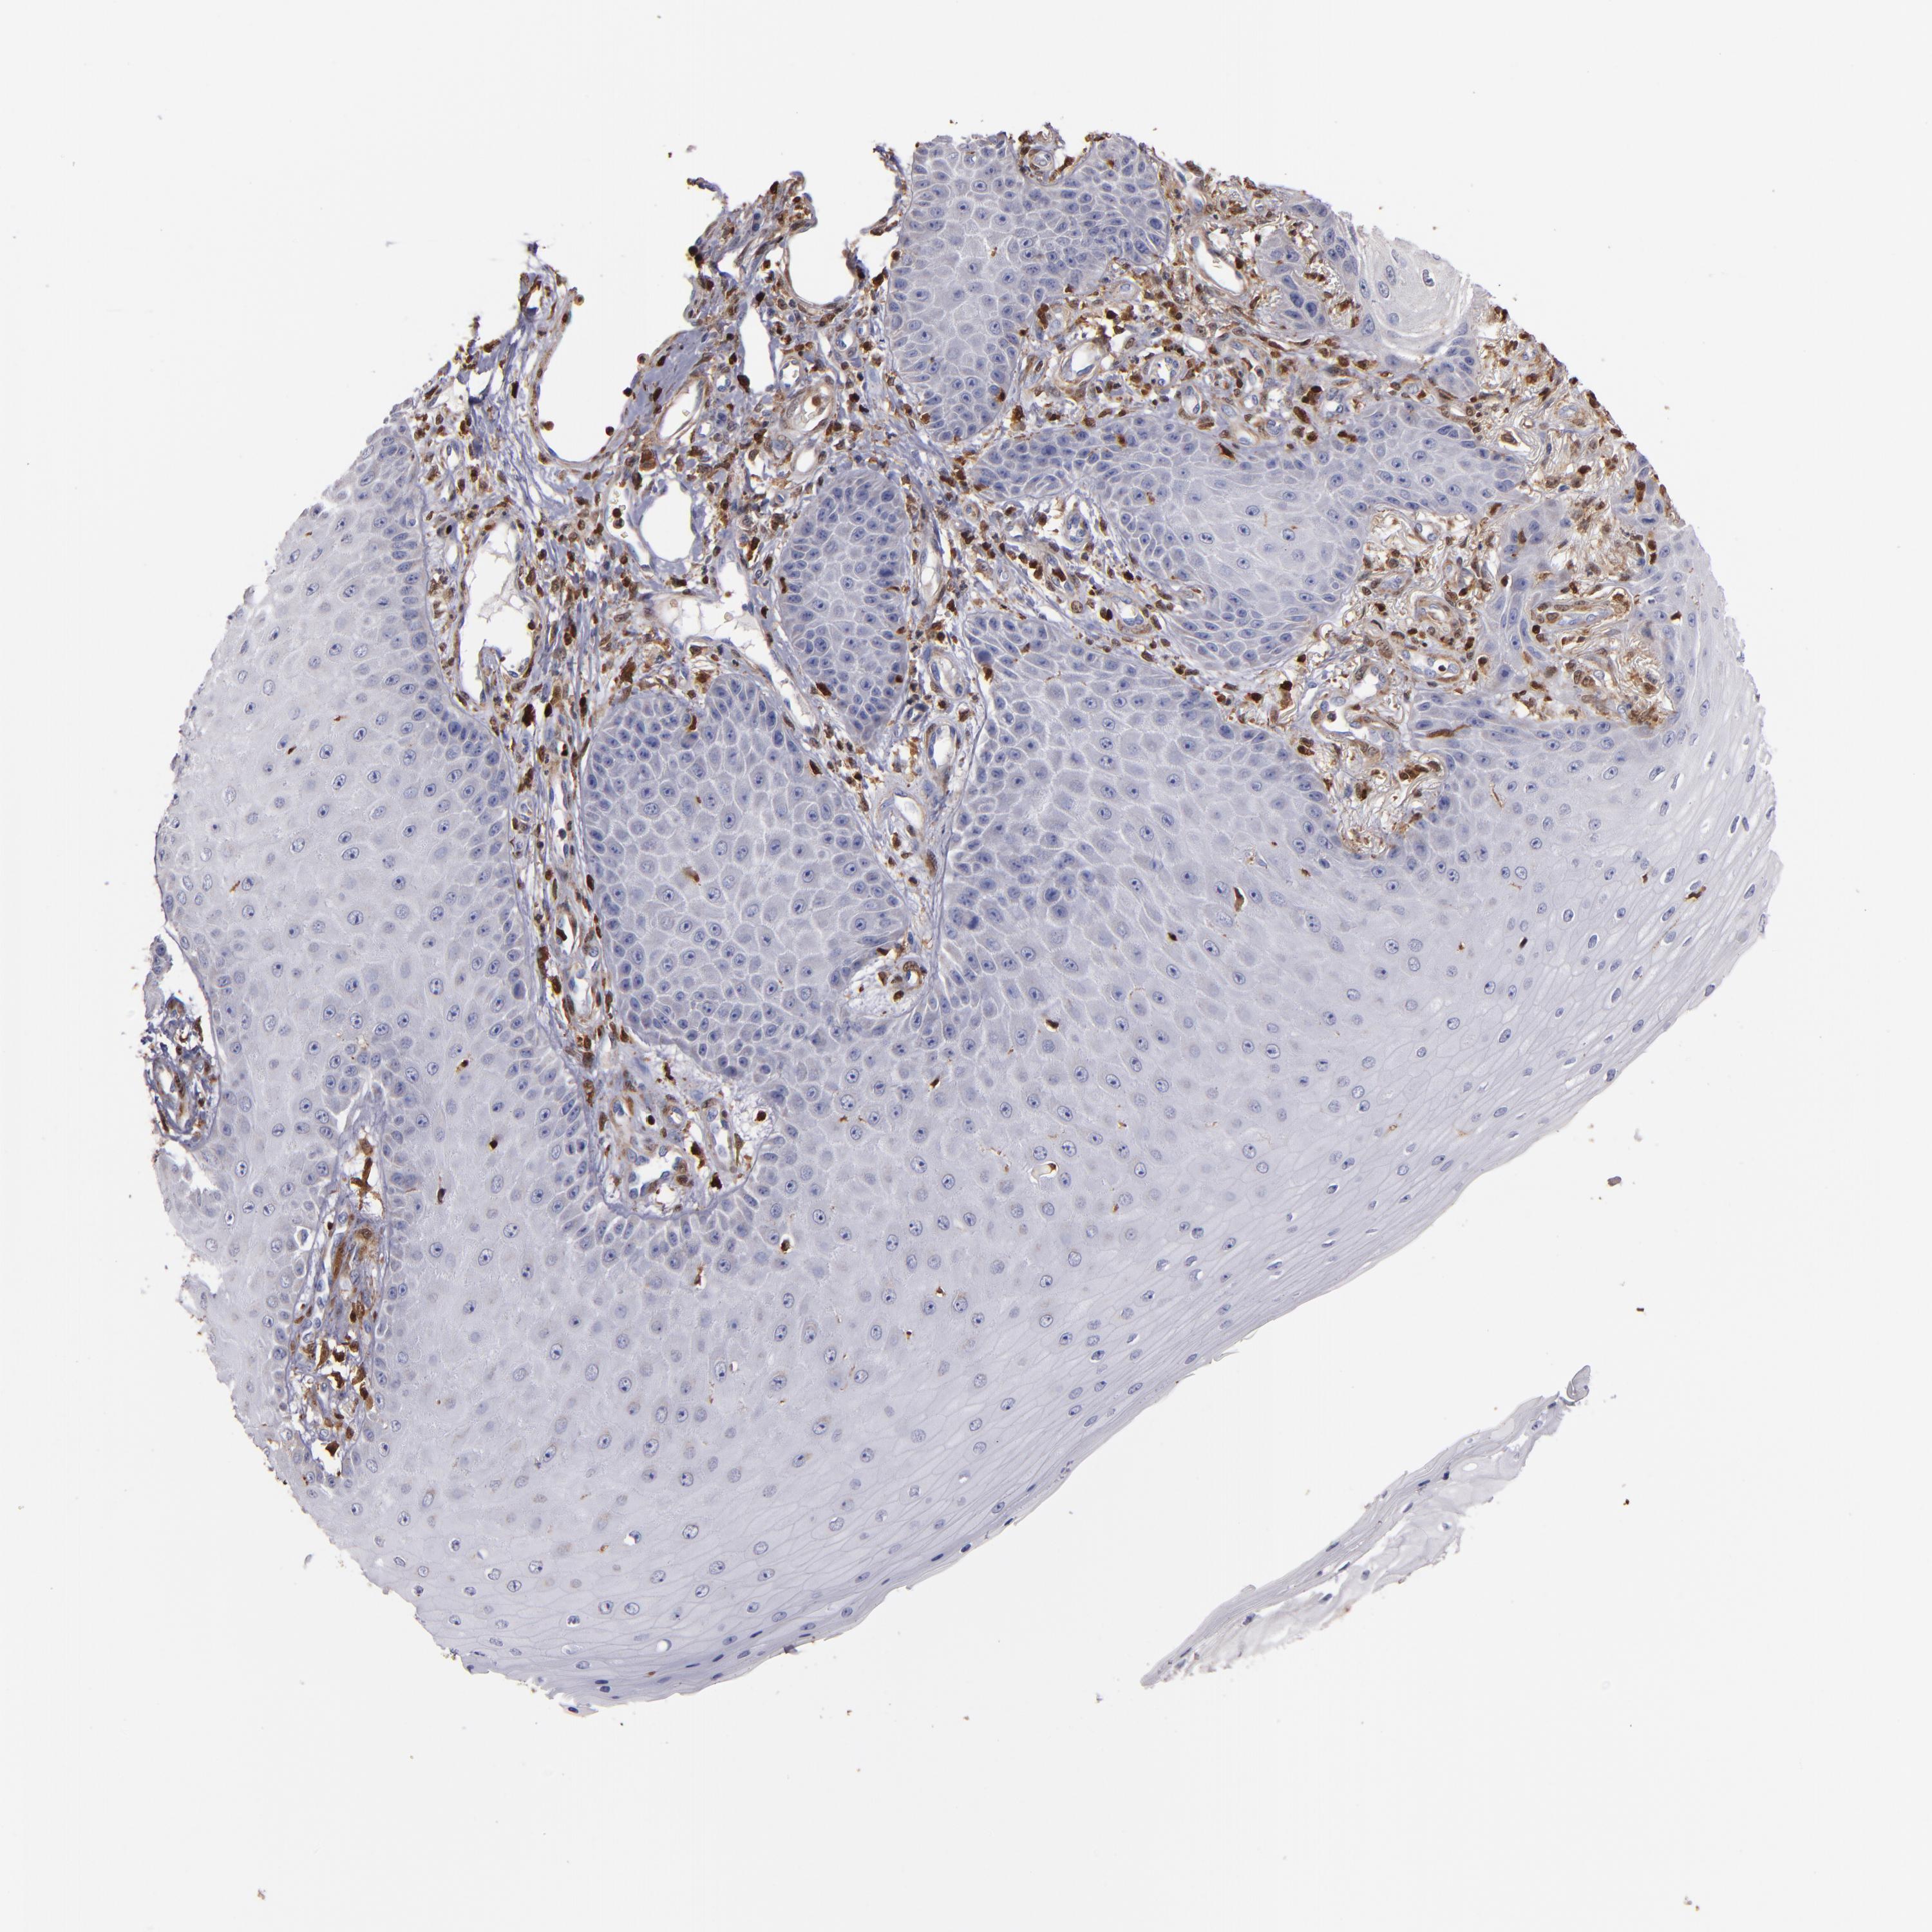

CANCER SKIN CANCER Show tissue menu

Basal cell and squamous cell cancer

SKIN CANCER - Protein expressioni

A mouse-over function shows sample information and annotation data. Click on an image to view it in a full screen mode. Samples can be filtered based on level of antibody staining by selecting one or several of the following categories: high, medium, low and not detected. The assay and annotation is described here.

Each image is clickable and will lead to virtual microscopy that enables deeper exploration of all samples and also displays staining intensity scores, fraction scores and subcellular localization as well as patient and tissue information for each sample.

HPA007973

Basal cell carcinoma